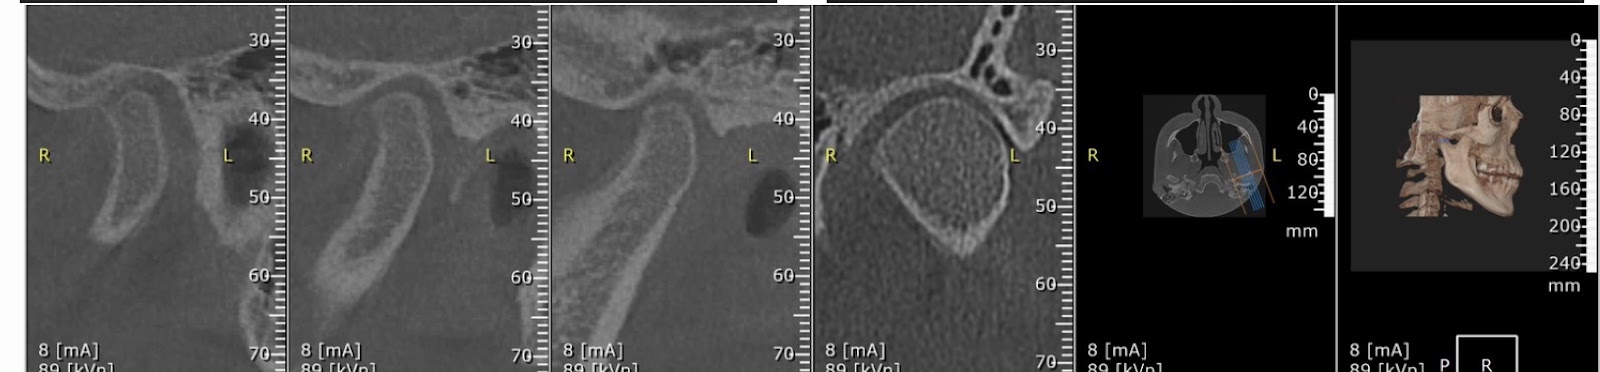

The results of the condylar reposition are shown in the pictures below!

Right side

Before condylar reposition

After condylar repositioning

Left side

Before condylar repositioning